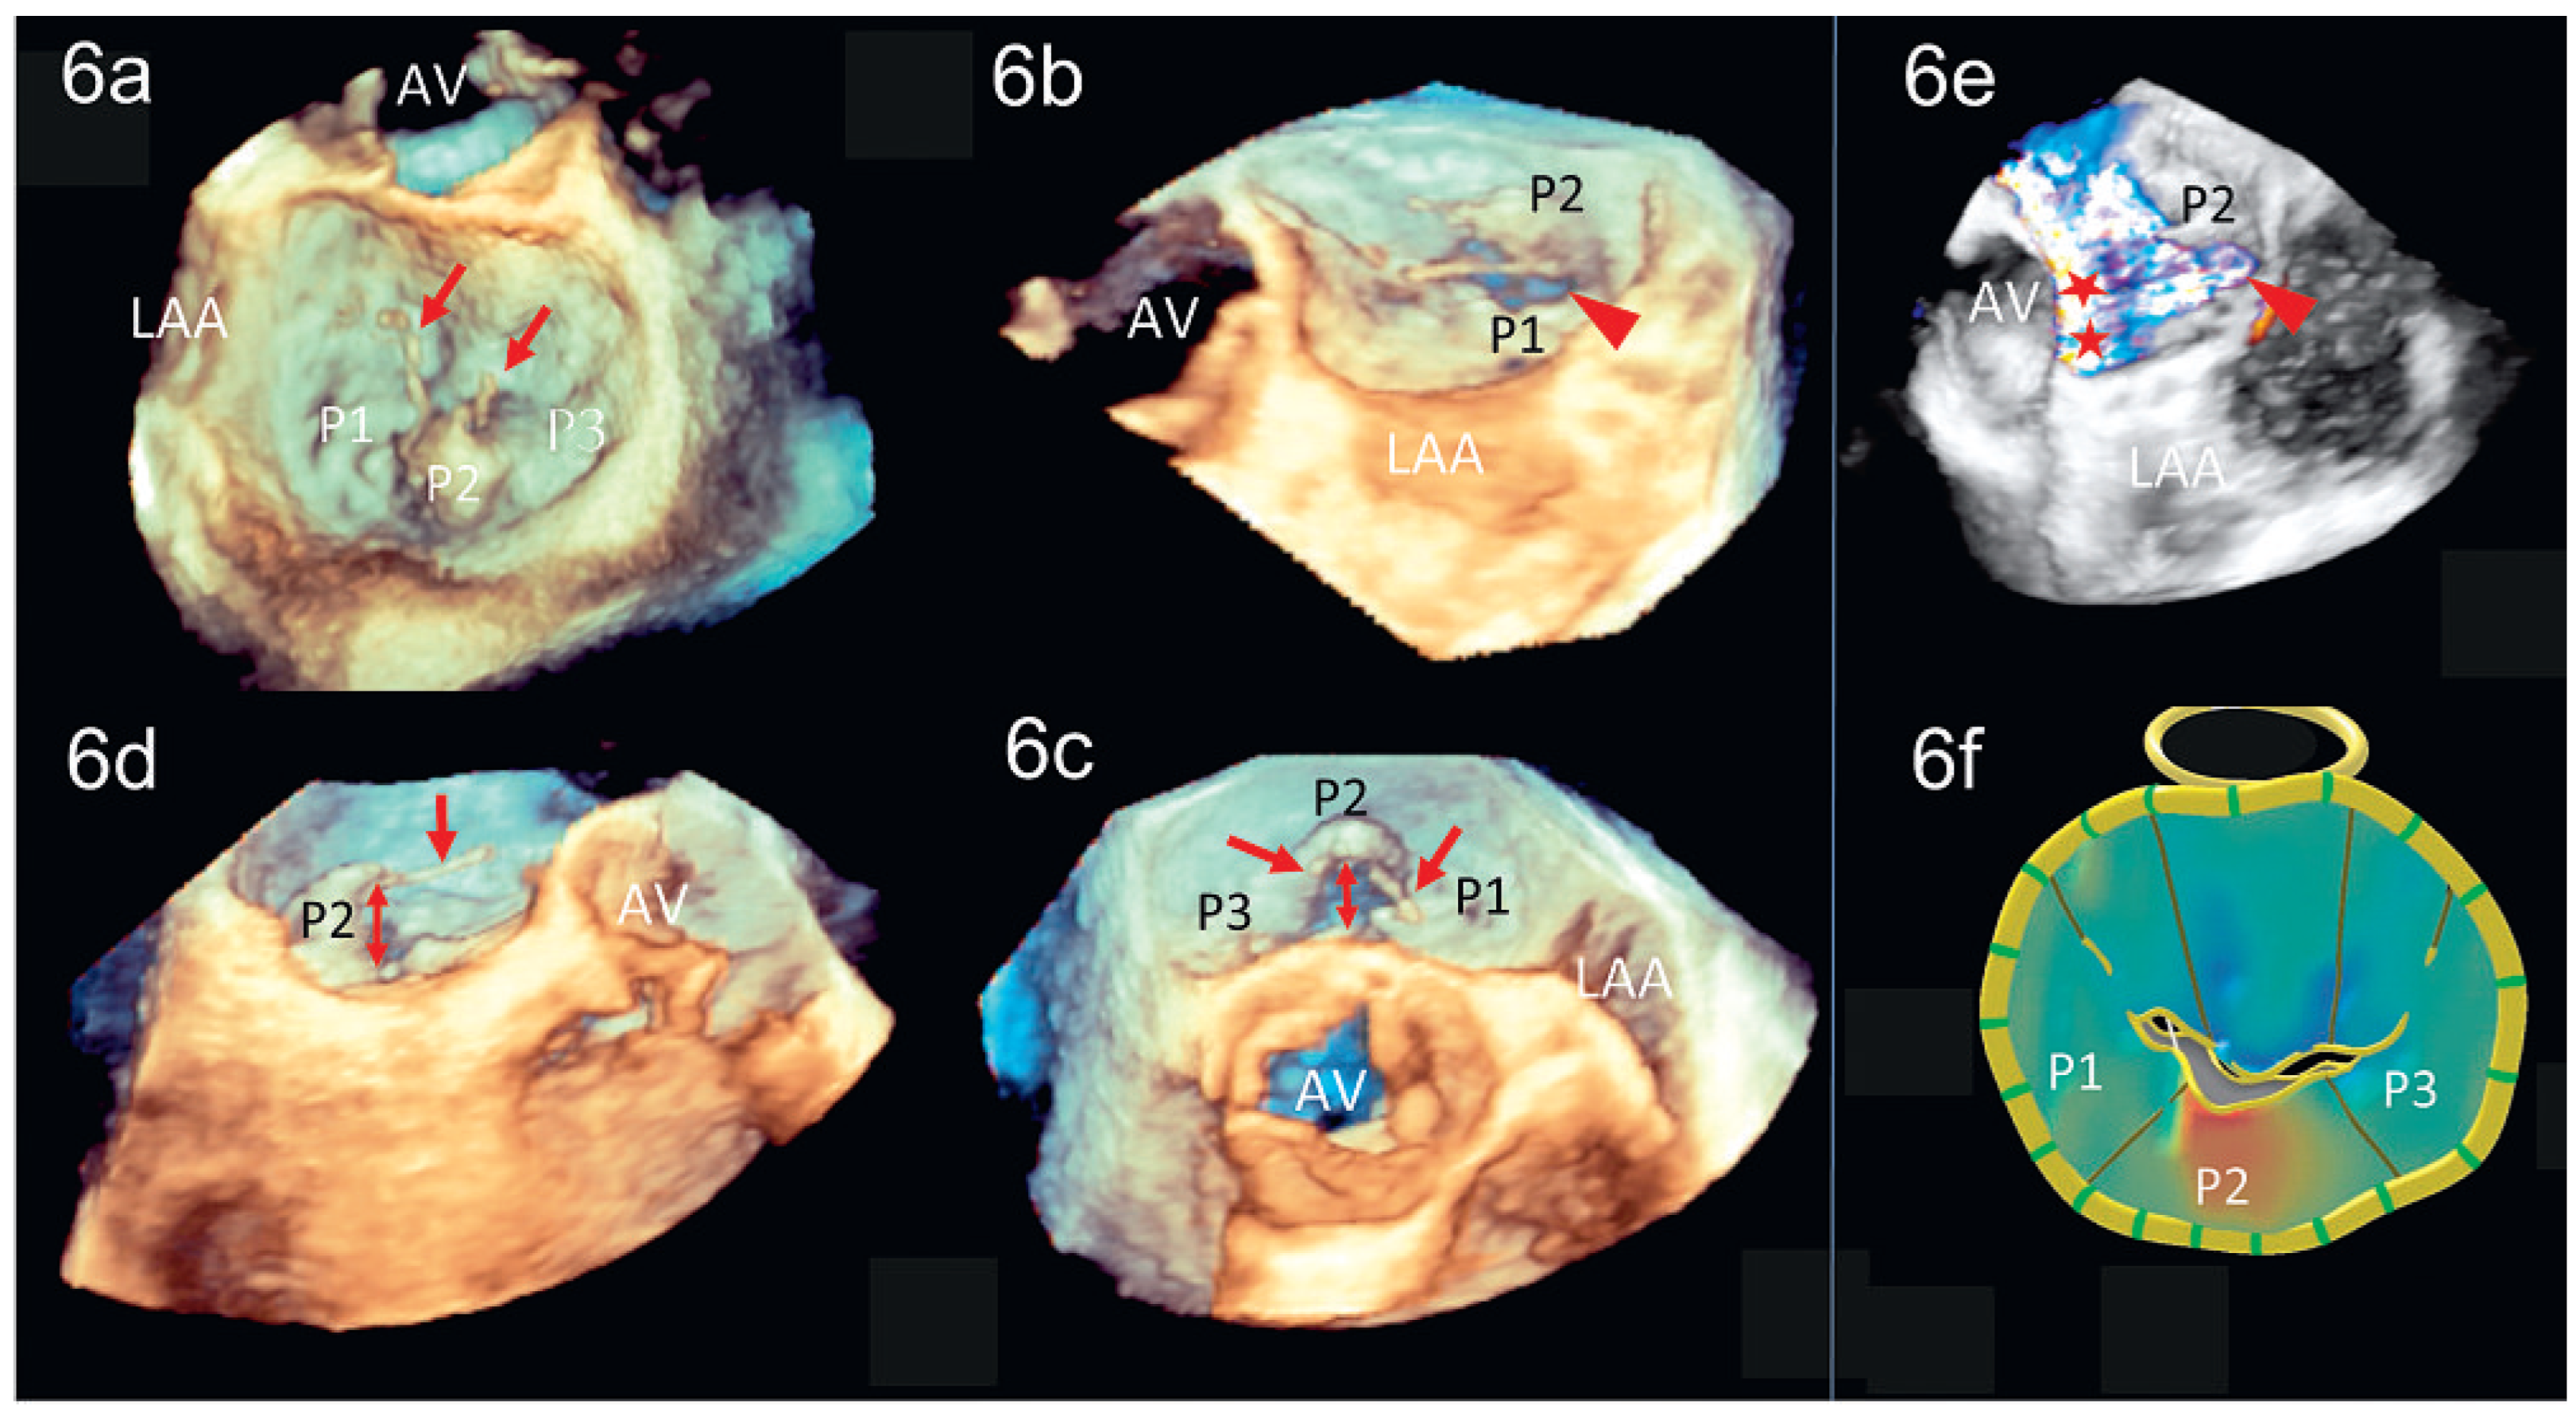

3D-TEE